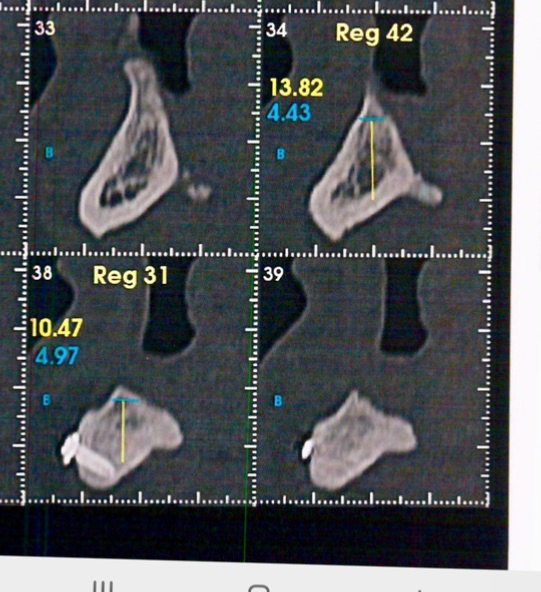

A cirurgia de reconstrução óssea estava contraindicada devido à qualidade ruim dos tecidos moles. Por conta disso, foi planejada uma cirurgia guiada para evitar o descolamento do tecido mole que fatalmente teria muita dificuldade para ter uma reparação satisfatória.

A escolha foi pelo implante Cone Morse Maestro, pois o osso era muito cortical e a macrogeometria do implante Maestro permite a colocação com um torque menor.

A cirurgia guiada foi fundamental na resolução desse caso, pois uma cirurgia com incisão e descolamento de tecido mole traria muitas dificuldades para a cicatrização.